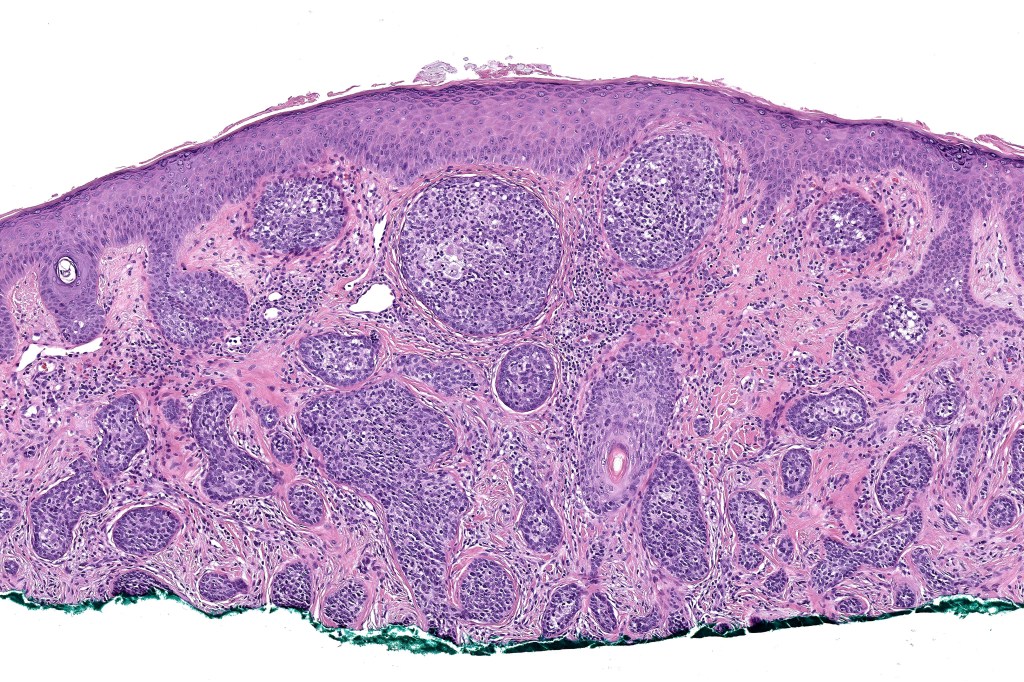

Histological features

•Dermal nodule, rarely extends into subcutaneous fat

•Irregular lobules of epithelial cells embedded in a dense fibrous stroma

•Peripheral rim of darkly staining basaloid cells surrounding larger pale staining cells with vesicular nuclei with often prominent eosinophilic nucleoli

•Central cells PAS positive (glycogen)

•No pleomorphism or mitotic activity

•No retraction artifact or stromal mucin

•Admixed lymphocytes (an obligatory feature)

•Germinal centers sometimes present